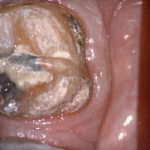

For the second molar, we will take advantage of the anesthesia time and capture the first bite, the opposing, the pre-existing situation and then crop out the preparation area digitally. Once the tooth is prepared, we will check for proper reduction. We will then take the second bite to verify the vertical dimension has not changed.

While the second molar is being designed and milled in the first case, we will launch a second window by cloning the first case. All the data remains the same and this time we crop out the first molar digitally and protect the rest of the arch. Once the first molar is isolated, it is digitally captured and then designed and milled.